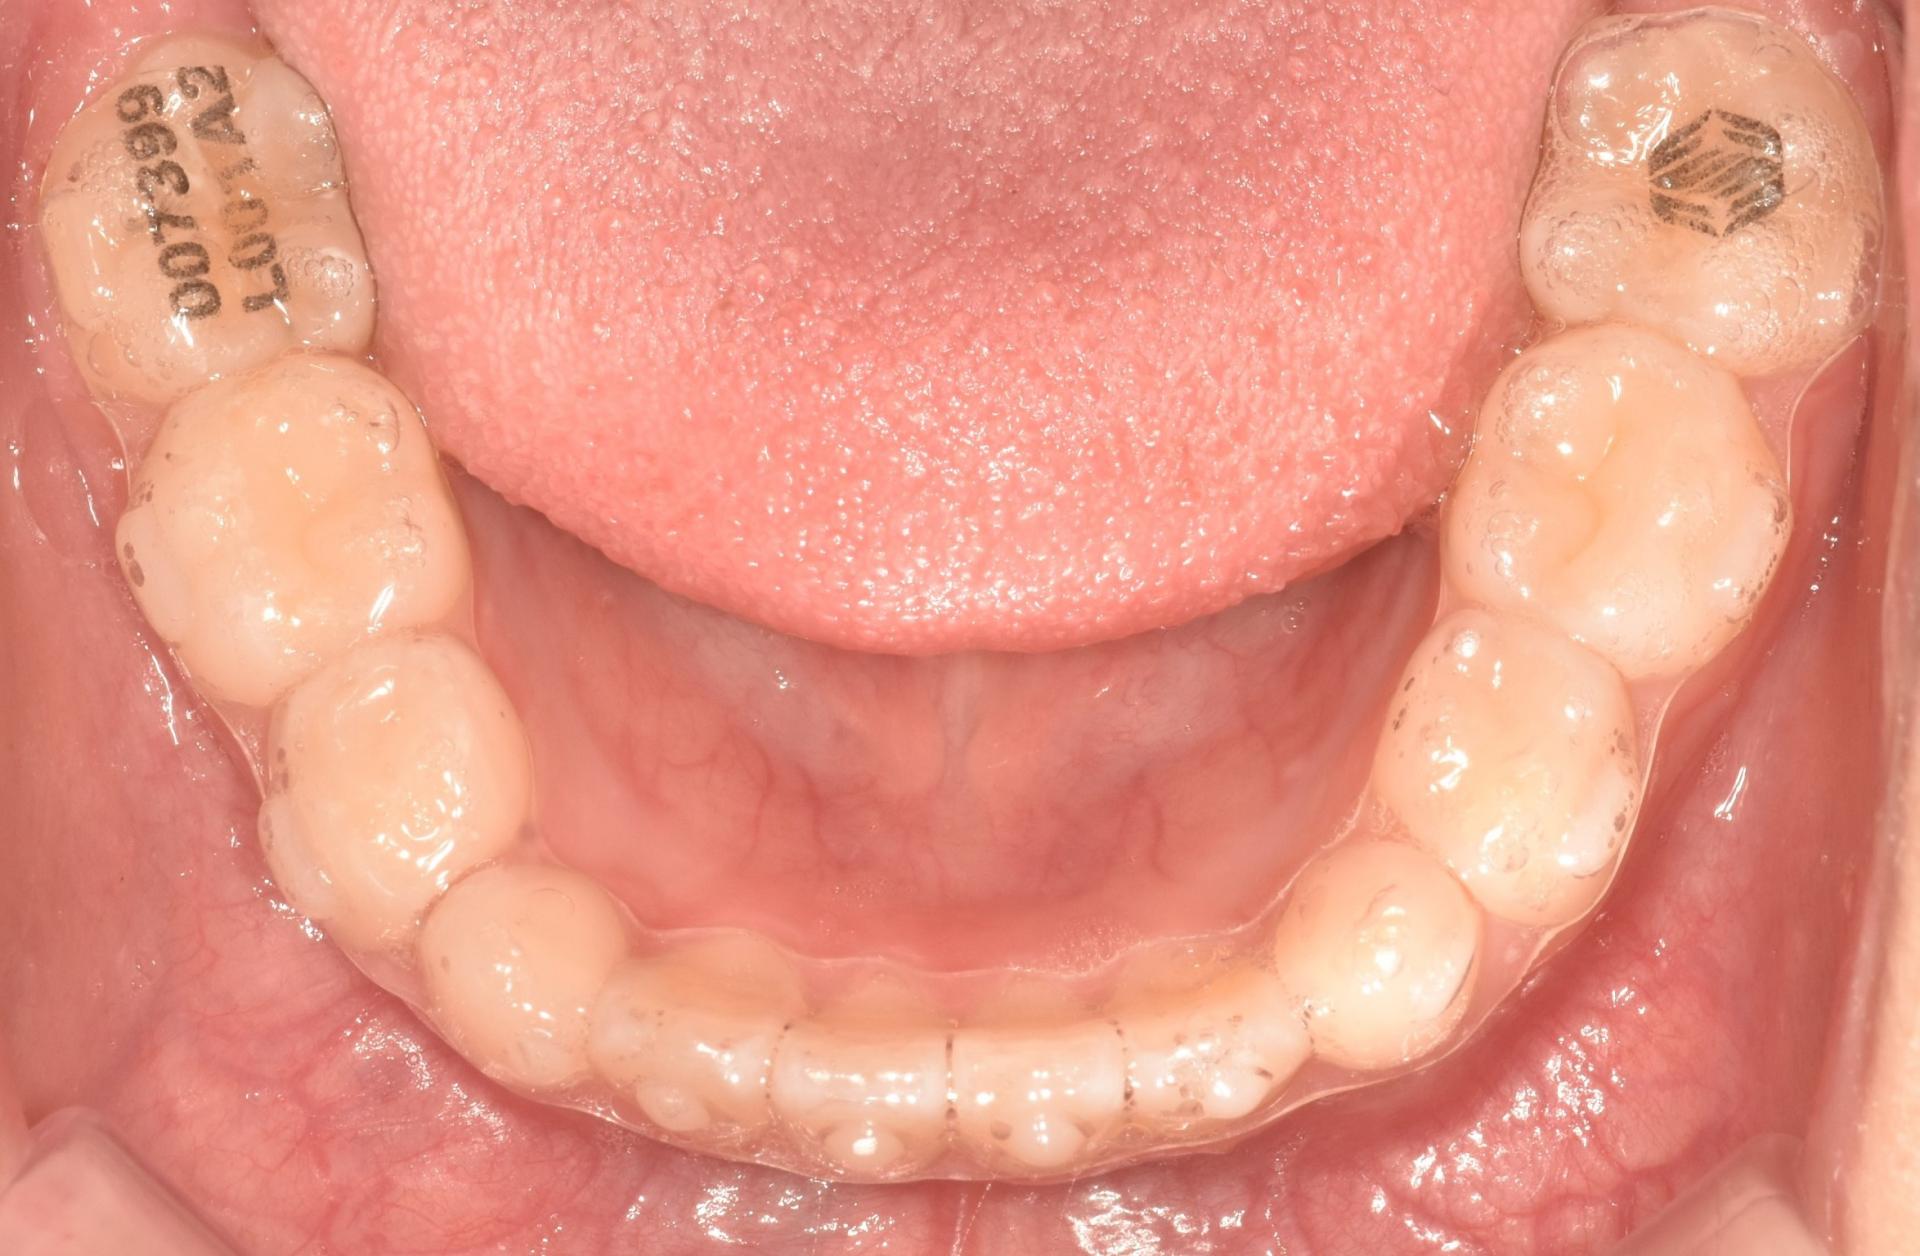

교정 진행중, 투명교정장치를 착용한 모습입니다. 치아위로 철사가 지나가지 않으니, 교정하는 것이 남들 눈에 띄지 않게, 편하게 뺏다 꼈다 하고, 철사 찔림이 발생하지 않으며 통증없이 치료를 진행할 수 있다는 장점이 있어 많은 어린이들이 선호하는 치료입니다!